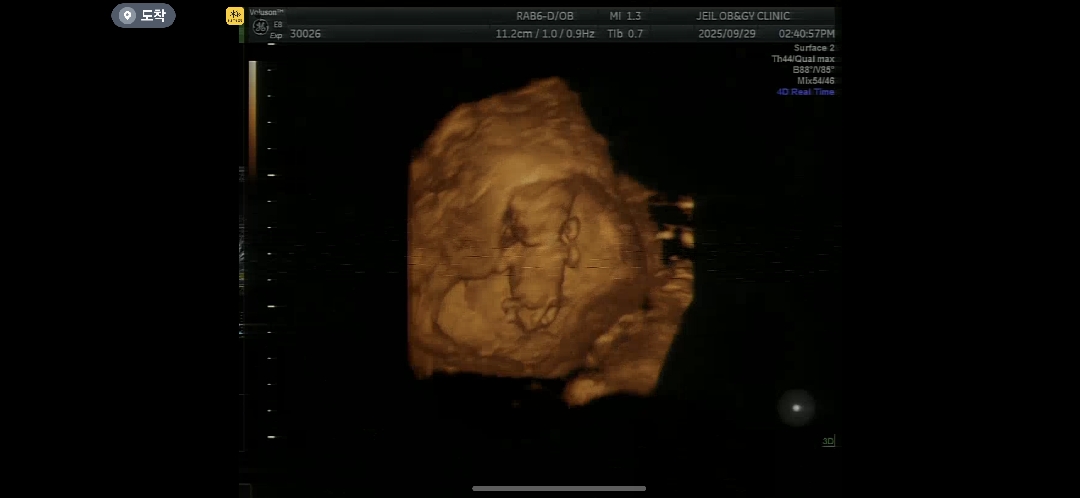

12주 입체 초음파 한번 봐주세요

이 사진으로 성별 유추 될까요?? ㅠ